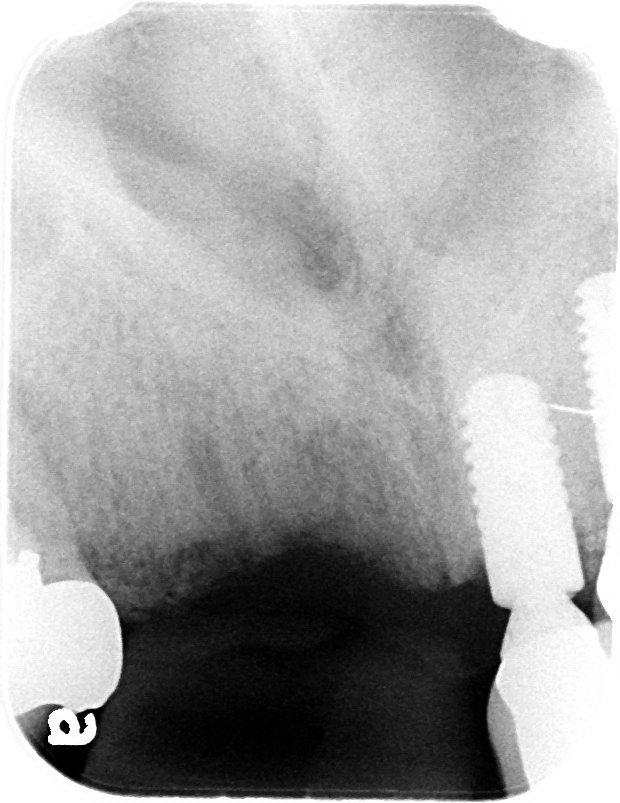

Pre-extraction